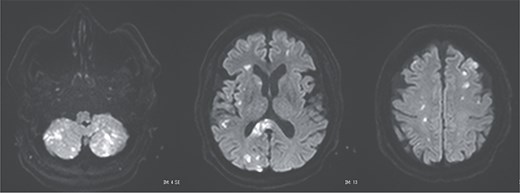

A 70-year-old woman presented to the emergency department with sudden-onset chest and back pain. Contrast-enhanced CT revealed an ATAAD extending from the ascending aorta to the bilateral common iliac arteries. The primary entry tear extended from the ascending aorta into the aortic arch, and the false lumen remained patent throughout its entire peripheral extent (Fig. 1). Both renal arteries originated from the true lumen, and there was no malperfusion. Vital signs were stable, and the patient was not in shock. The patient underwent emergency total arch replacement with FET implantation using a 27 × 90 mm FROZENIX four-branched graft (Japan Lifeline Co., Ltd, Tokyo, Japan). The procedure was completed in 7 h and 6 min without intraoperative complications. Postoperatively, urine output declined markedly. Serum creatinine increased from a baseline of 0.81 to 2.61 mg/dl on postoperative Day 1. Diuretics failed to improve urine output, and renal replacement therapy was initiated. Contrast-enhanced CT on postoperative Day 2 showed no signs of renal malperfusion. Although the renal medulla exhibited normal enhancement, a diffuse non-enhancing area throughout the renal cortex—referred to as the “reverse rim sign”—was observed, consistent with RCN (Fig. 2). Thrombosis of the false lumen in the descending thoracic and thoracoabdominal aorta had progressed (Fig. 3). The patient developed persistent coagulopathy, with sustained hypofibrinogenemia and thrombocytopenia. On postoperative Day 2, the platelet count was 4.1 × 104/μl, D-dimer 13.5 μg/ml, and PT-INR 1.54, yielding an International Society on Thrombosis and Hemostasis DIC score of 6, consistent with overt DIC. Anticoagulation therapy with heparin and warfarin was administered. Ultimately, by postoperative Day 50, a total of 36 units of fresh frozen plasma and 100 units of platelets had been transfused; however, coagulation parameters gradually normalized thereafter, and no further transfusions were required (Fig. 4). A follow-up CT on postoperative Day 21 demonstrated further remodeling of the thrombosed false lumen. Brain magnetic resonance imaging performed on postoperative Day 9 to investigate delayed emergence revealed multiple scattered small acute ischemic infarctions involving the cerebellum, brainstem, and cerebral cortex (Fig. 5). These were not attributed to large-vessel occlusion but rather to systemic microthrombotic emboli. Despite supportive care, renal function did not recover, and maintenance dialysis was initiated. The patient was transferred to another hospital on postoperative Day 182.

Postoperative magnetic resonance imaging showing diffuse cerebral infarctions.